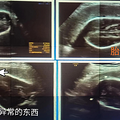

日前,一名来自安顺农村的孕妇王女士,在医院做四维彩超时,发现腹中胎儿无脑无颈,四肢发育不全,在医生的建议下,已近8个月的胎儿被迫引产。王女士后悔的表示,如果能早些做检查,就不会这么晚才发现胎儿有问题。 王女士已怀孕31周,来到妇产医院检查。在彩超过程中,医生发现王...